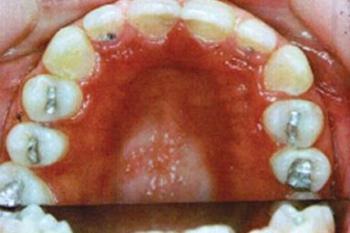

Klinikai kép. A klinikai képet a palatum erős hyperaemiája jellemzi, de azok a területek, melyeket a fogsor fed, nem tünnek érintettnek. Ha a fogsor alatt kiemelkedő terület van, úgy nézhet ki, mintha granuláció lenne, hyperplasticus forma (5.4. ábra, 5.5. ábra). Ezekre a klinikai állapotokra Newton egy lehetséges osztályozást vezetett be (5.5. táblázat).

5.4. ábra. Pseudomembranosus candidiasis